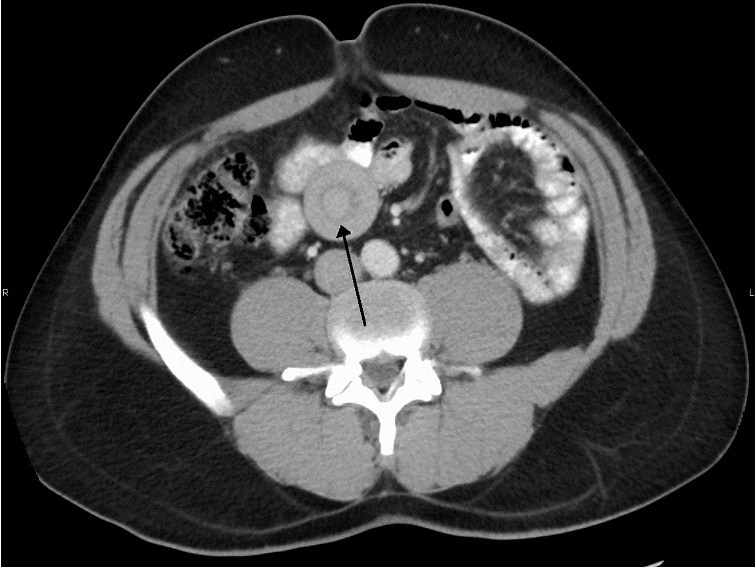

Abdominal CT: Perform if ultrasound and abdominal x-ray are inconclusive.

Target sign in intussusception Ultrasound abdomen (bowel; transverse plane) Concentric alternating hyperechoic and hypoechoic rings are visible. The hyperechoic rings (green overlay) are formed by mucosa and the hypoechoic rings (red overlay) by submucosa. Together the alternating layers produce a target-like appearance (target sign; bull’s eye sign).